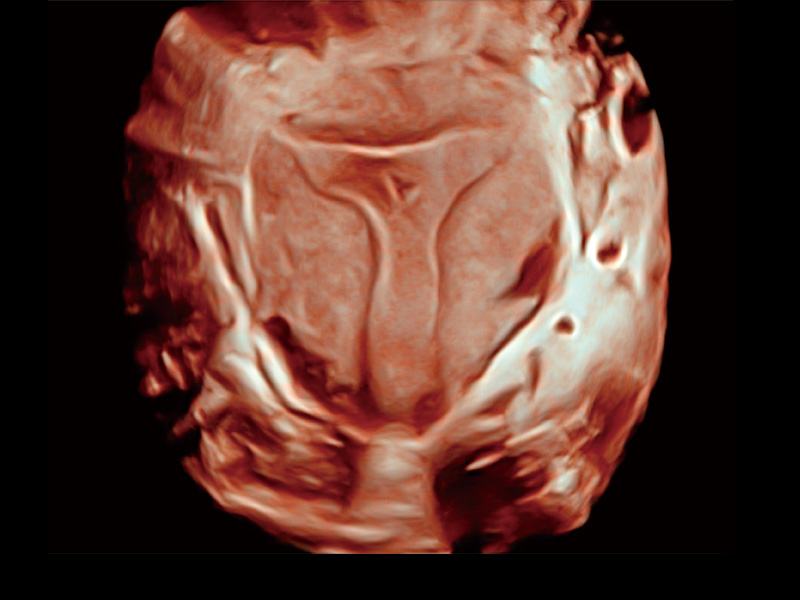

“生育问题”即关系民族复兴,也关系亿万家庭的幸福。随着婚育年龄推迟、社会压力增加等因素,越来越多人群也面临着“生不出、生不好”的问题。辅助生殖作为治疗不孕不育最有效的方法之一,也逐渐成为育儿新希望。而超声检查能为生殖需求人群的初诊评估提供宝贵的信息。 P20 Elite是玖鼎集团匠心打造的一款生殖应用型彩超。她继承玖鼎集团高端极光平台,突破性地将多款新型芯片及硬件模块进行整合,均衡了高端系统性能与小巧灵动机身。P20 Elite卓越的图像质量搭载专科探头,旨在为您提供全面的辅助生殖解决方案。

P20 Elite配备了丰富的生殖探头群和临床应用功能,在卵泡监测、穿刺取卵、胚胎移植、妊娠确认等领域,为生殖需求人群提供了新的临床机会,重新定义高端超声如何应用于生殖健康检查。